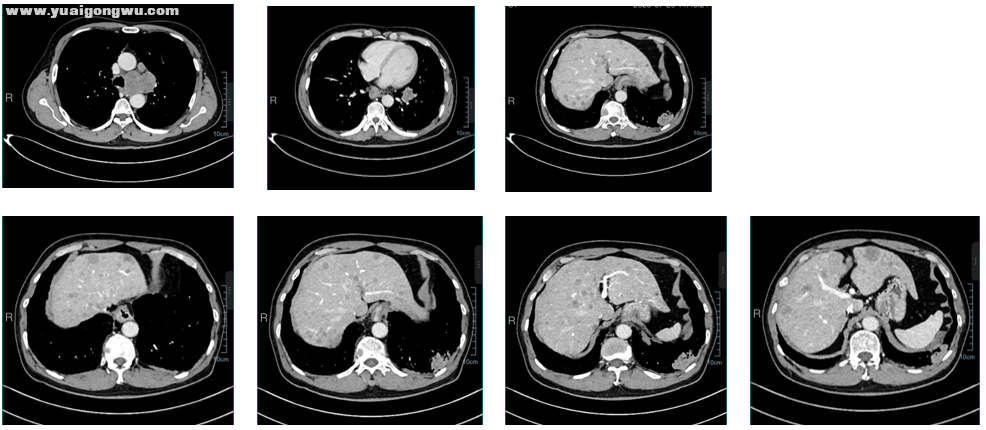

患者概况: 65岁男性,身高165cm,体重61kg,既往无基础病; 患者2025年7月就诊于湖南省直中医院,腹部增强CT(2025-7-28):肝实质内弥漫大小不等弱强化结节,考虑转移瘤可能性大。 2025年7月29颈胸增强CT:左下肺外基底段及左肺下叶前内基底段新见肿块,考虑恶性肿瘤(肺癌并肺内转移可能性大);左侧胸膜局部增厚不均匀强化:考虑转移;左锁骨上窝、纵隔及左肺门多发肿大淋巴结:转移性淋巴结可能性大;左侧第6后肋、胸椎及胸骨多发溶骨性骨质破坏:考虑骨转移瘤,右侧髂骨成骨性改变。肝实质内弥漫大小不等弱强化结节,考虑转移瘤可能性大;余双肺多发小结节,部分新见,转移待排,建议追踪复查。 2025年7月30日头部增强MRI:脑萎缩;颅内未见异常强化灶。 确诊为:左肺下叶小细胞癌(T2N3M1c IVB期),左肺门、纵隔及左侧锁骨上淋巴结转移、肝转移、骨转移; 其他诊断:慢性阻塞性肺疾病、双肺间质纤维化、左肾囊肿;

5 X$ {; s1 R, B: G治疗过程: 一线治疗:2025-8-5 至2025-11-25行EP方案+阿替利珠单抗治疗4周期,阿替利珠单抗维持治疗2周期,地舒单抗治疗骨转移; / s) X( Z0 h! Q: m5 H' k

一线治疗效果如下: 由于患者从后颈到前额阵发性头晕头痛,紧急入院检查核磁(2026年1月12日)。化放同时患者头晕、头痛、呕吐,进食少,输营养液。

李成海教授(影像科) 梳理患者全部影像资料如下:2025年7月份初始胸部CT提示,左下叶有两个病灶,伴左胸膜增厚,左锁骨上、左肺门淋巴结转移,同时存在骨转移及肝脏多发转移。经治疗后,肝脏转移灶治疗效果显著,逐渐减少,后续多个治疗周期后,肝脏转移灶基本消失。2026年1月12日头部增强核磁显示,大脑脑膜、颅内出现转移灶及强化结节;1月24日复查CT对比2025年12月11日结果,左下叶外基底段病灶稍增大,胸膜增厚与既往一致,同时出现淋巴结增大及双肺新增小结节。结合影像表现,相较于治疗最佳时期,当前病灶增大、双肺新增小结节,转移概率较高。因目前不清楚新增结节具体大小,建议进一步行CT等检查完善评估。

, q. D# A+ g( @8 o- _* W胡瑛教授(肿瘤中心) 从影像资料来看,患者前期治疗效果显著,肺内及肝脏病灶均得到良好控制。但小细胞肺癌的生物学行为决定其恶性程度高,即便前期疗效理想,也可能快速进展,患者出现中枢神经系统转移(脑转移合并脑膜转移),正符合该疾病特点,虽令人惋惜,但也属临床常见情况。脑转移本身治疗难度较大,合并脑膜转移后治疗更为棘手,结合当前病情,患者预后不容乐观。不过,二线治疗中启用芦比替定较为及时,该药物获批小细胞肺癌二线适应症,相关研究显示其对脑转移也有一定治疗效果,目前用药时间较短,疗效尚未能明确判断。